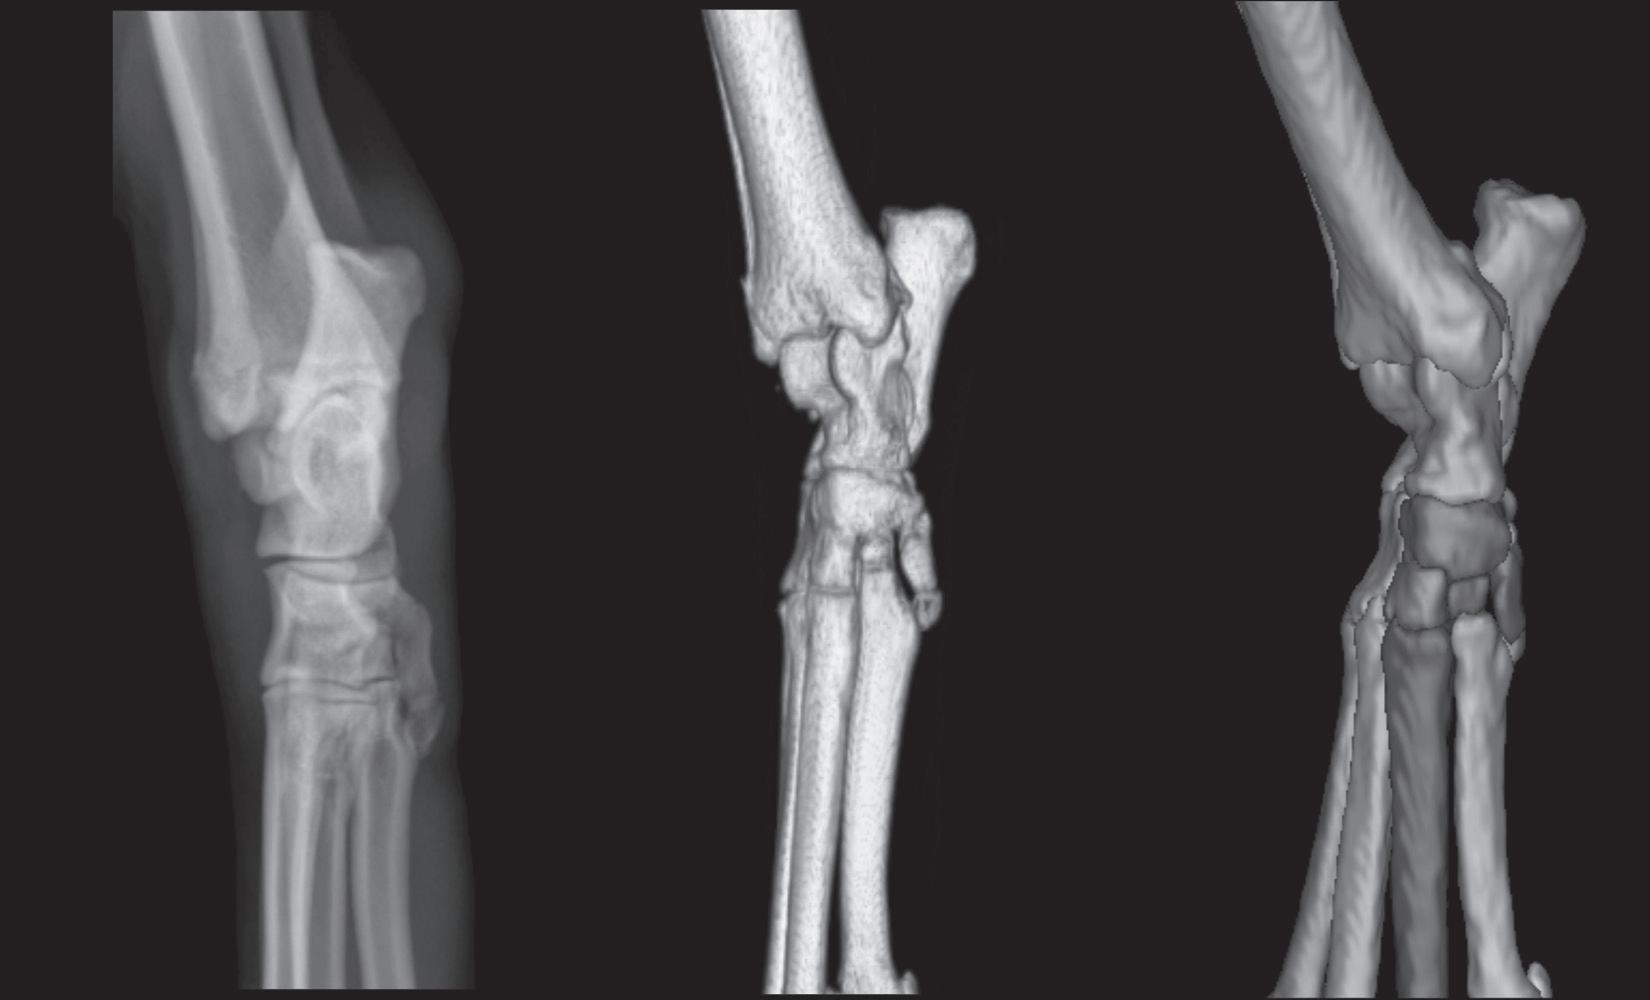

Figure 1-8. The left panel is a dorsoplantar radiograph of a canine tarsus. The middle panel is a three-dimensional rendering of a normal right canine tarsus from the perspective of the x-ray beam when making a dorsoplantar radiograph. The right panel is identical to the middle panel, except each bone has been colorized (see Color Plate 1). Colorizing makes it easier to comprehend the extent of overlap. Note in the radiograph that the only edges that can be evaluated are the medial and lateral edges.